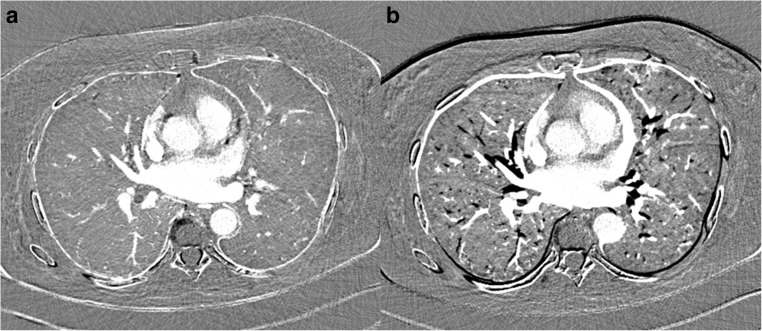

Fig. 1.

1-mm axial CTPA reconstructions after subtraction of an unenhanced CT from a CTPA with a diaphragm difference of 11 mm between the scans. a With motion correction, and (b) without motion correction